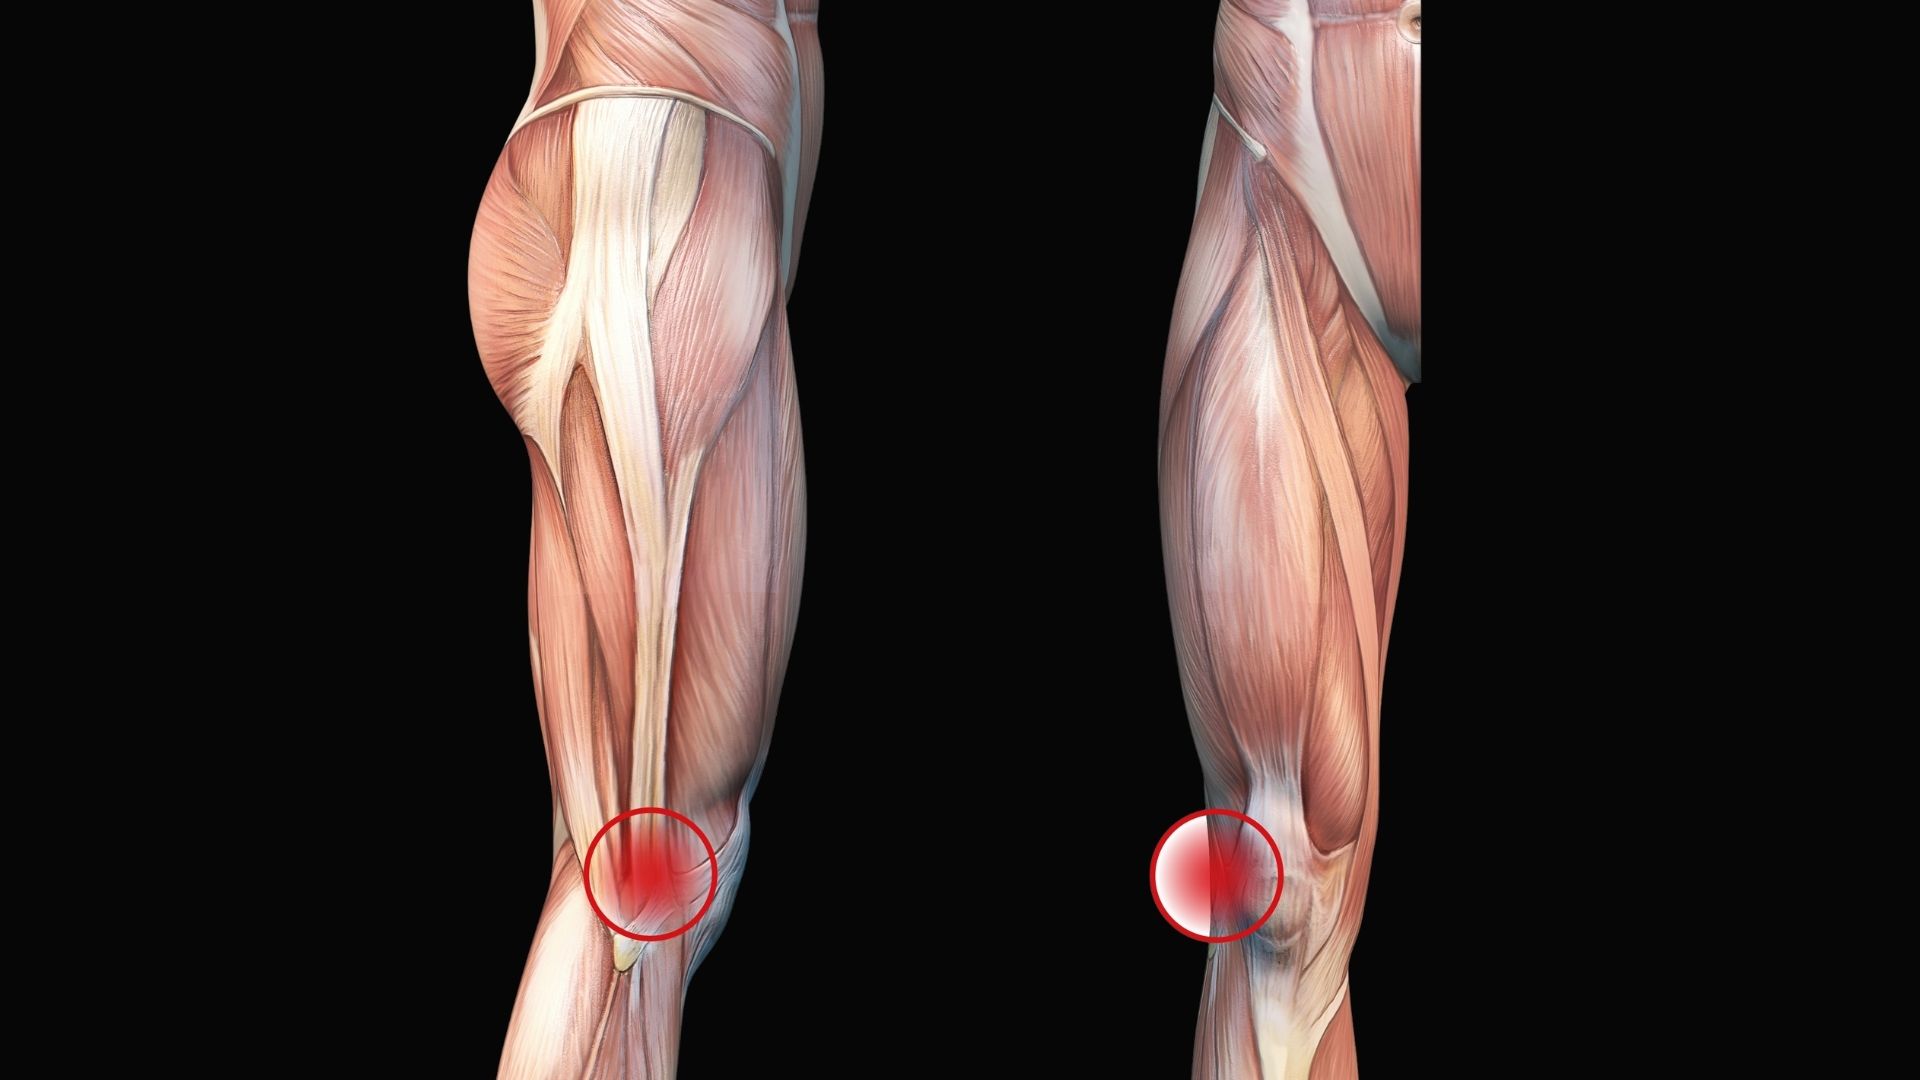

What if the root of your client’s knee, hip, or back pain starts with their big toe? What if overlooked midfoot restrictions are driving compensation up the kinetic chain? In this video demonstration, Erik teaches a series of simple, effective foot mobilizations you can easily integrate into your sessions.